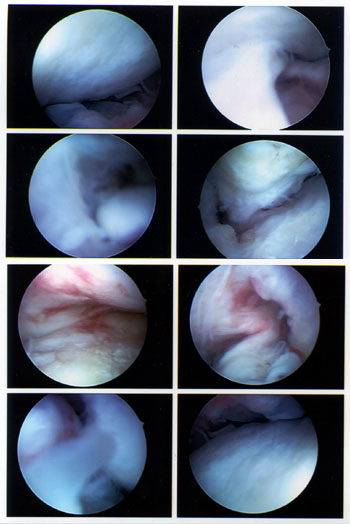

Und wer will, kann sich hier noch die Fotos aus dem Inneren anschauen - klicken für grössere Fassung:

Arthsoskopiefotos 9. Mai 2008; Klicken für grosse Fassung